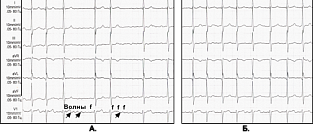

Влияние факторов риска на сохранение синусного ритма при фибрилляции предсердий

На ежегодном конгрессе Европейского общества кардиологов (ESC) были представлены результаты рандомиз...

16.10.2017 3966 #фибрилляция предсердий #синусовый ритм